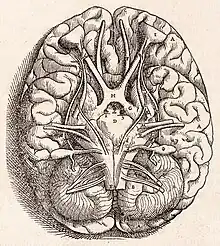

The brain is the central organ of the human nervous system, and with the spinal cord makes up the central nervous system. The brain consists of the cerebrum, the brainstem and the cerebellum. It controls most of the activities of the body, processing, integrating, and coordinating the information it receives from the sense organs, and making decisions as to the instructions sent to the rest of the body. The brain is contained in, and protected by, the skull bones of the head.

The cerebrum, the largest part of the human brain, consists of two cerebral hemispheres. Each hemisphere has an inner core composed of white matter, and an outer surface – the cerebral cortex – composed of grey matter. The cortex has an outer layer, the neocortex, and an inner allocortex. The neocortex is made up of six neuronal layers, while the allocortex has three or four. Each hemisphere is divided into four lobes – the frontal, temporal, parietal, and occipital lobes. The frontal lobe is associated with executive functions including self-control, planning, reasoning, and abstract thought, while the occipital lobe is dedicated to vision. Within each lobe, cortical areas are associated with specific functions, such as the sensory, motor, and association regions. Although the left and right hemispheres are broadly similar in shape and function, some functions are associated with one side, such as language in the left and visual-spatial ability in the right. The hemispheres are connected by commissural nerve tracts, the largest being the corpus callosum.

The cerebrum is connected by the brainstem to the spinal cord. The brainstem consists of the midbrain, the pons, and the medulla oblongata. The cerebellum is connected to the brainstem by three pairs of nerve tracts called cerebellar peduncles. Within the cerebrum is the ventricular system, consisting of four interconnected ventricles in which cerebrospinal fluid is produced and circulated. Underneath the cerebral cortex are several important structures, including the thalamus, the epithalamus, the pineal gland, the hypothalamus, the pituitary gland, and the subthalamus; the limbic structures, including the amygdalae and the hippocampi, the claustrum, the various nuclei of the basal ganglia, the basal forebrain structures, and the three circumventricular organs. Brain structures that are not on the midplane exist in pairs, for example, there are two hippocampi and two amygdalae. The cells of the brain include neurons and supportive glial cells. There are more than 86 billion neurons in the brain, and a more or less equal number of other cells. Brain activity is made possible by the interconnections of neurons and their release of neurotransmitters in response to nerve impulses. Neurons connect to form neural pathways, neural circuits, and elaborate network systems. The whole circuitry is driven by the process of neurotransmission.